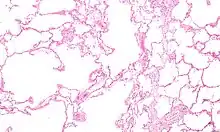

| Micrograph of an emphysematous lung; emphysema is a rare respiratory disease, strongly associated with smoking. H&E stain. | |

Obstructive lung disease

Asthma, chronic bronchitis, bronchiectasis and chronic obstructive pulmonary disease (COPD) are all obstructive lung diseases characterised by airway obstruction. This limits the amount of air that is able to enter alveoli because of constriction of the bronchial tree, due to inflammation. Obstructive lung diseases are often identified because of symptoms and diagnosed with pulmonary function tests such as spirometry. Many obstructive lung diseases are managed by avoiding triggers (such as dust mites or smoking), with symptom control such as bronchodilators, and with suppression of inflammation (such as through corticosteroids) in severe cases. One common cause of COPD including emphysema, and chronic bronchitis, is tobacco smoking, and common causes of bronchiectasis include severe infections and cystic fibrosis. The definitive cause of asthma is not yet known.[4]